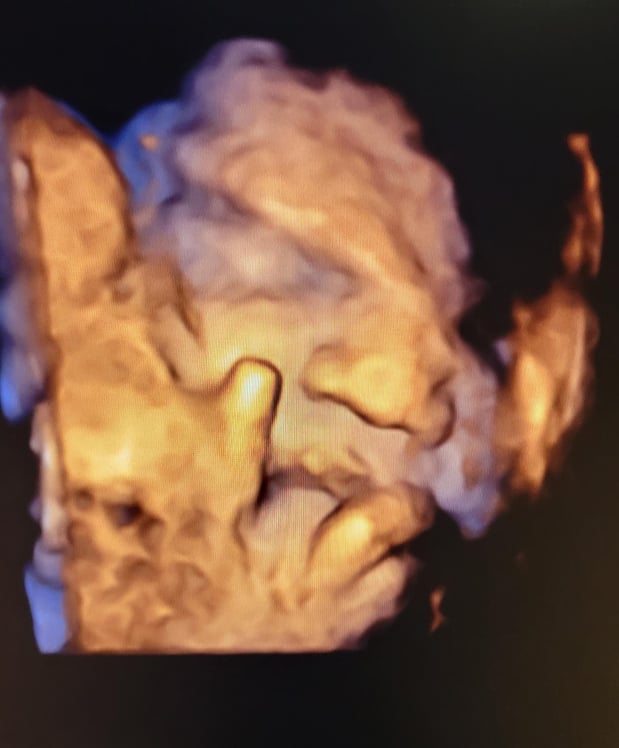

Tasha Crump, is registered by the American Registry of Diagnostic Medical Sonographers (ARDMS) and have over 18 years experience in medical diagnostic sonography specializing in Maternal Fetal Medicine. She is a highly proficient in the art of 3D 4D ultrasound. Tasha has practiced and trained in NYC's top ranked hospitals including Columbia Presbyterian. At Love at First Sight Imaging Studio you'll be in a very comfortable and calming atmosphere for you and your family to bond with your baby. We have state of the art equipment with HD Live to image unbelievably realistic views of your baby. You will fall in Love at First Sight.